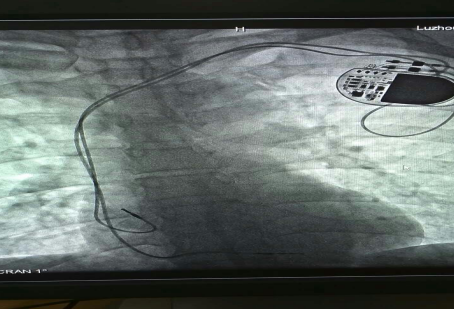

已安裝好的起搏系統(tǒng)

在征得患者及家屬的同意后,我院為其實(shí)施了雙腔永久心臟起搏器植入術(shù),該手術(shù)在瀘州市市屬醫(yī)院中率先使用磁共振兼容起搏電極,為患者未來(lái)有可能接受的磁共振檢查創(chuàng)造了條件。

已安裝好的磁共振兼容起搏電極